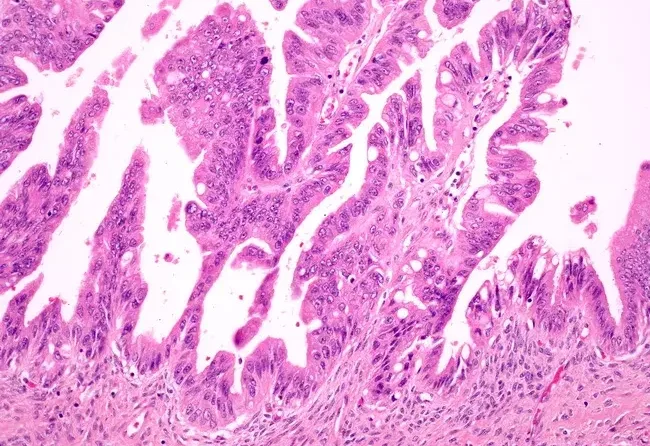

2. Malign Neoplazmalar (Kötü Huylu Tümörler ve Kanser)

Malign neoplazmalar, kanserli tümörlerdir ve genellikle hızla büyür, çevre dokulara yayılır (metastaz yapar) ve tedavi edilmediklerinde ölümcül olabilirler. Malign tümörler, vücutta sıklıkla farklı organlara yayılabilen ve invaziv davranış sergileyebilen kanser hücrelerinden oluşur. Kanserli hücreler, vücuda yayıldıkça organların işlevlerini bozabilir ve önemli sağlık sorunlarına yol açabilir.